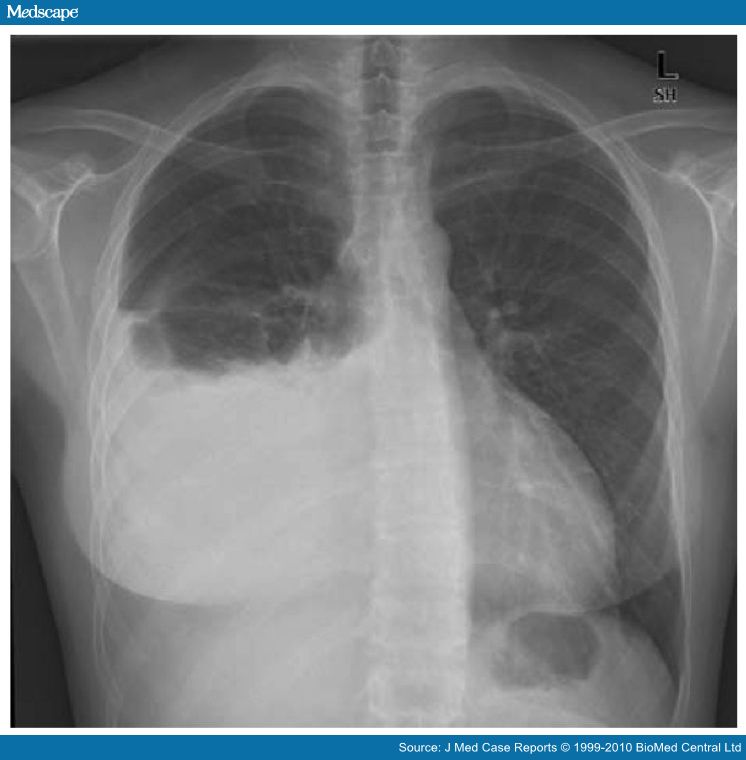

نضع بين ايديكم مجموعة الصور الاضافية على السلايدات التي تم شرحها في X-ray session :

Hydrothorax